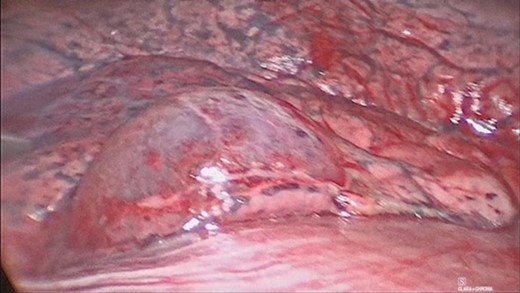

The patient was urgently reviewed by the cardiothoracic surgeons, and a small-bore chest tube was inserted, following which a computed tomography of the thorax was performed. This showed a residual but smaller pneumothorax with the chest tube in situ, associated with a small hemothorax (Fig. 3). Due to failure of conservative management and concern of a bronchopleural fistula resulting in air leak, he underwent explorative thoracoscopic surgery. Intraoperatively, an area of lung was noted with contusional changes and a bleb (Fig. 4), and a wedge resection of the right lower lobe was performed (Fig. 5). He made an uneventful recovery and was discharged.

Video assisted thoracoscopic surgery showing an area of right lung associated with a bleb and contusional changes.